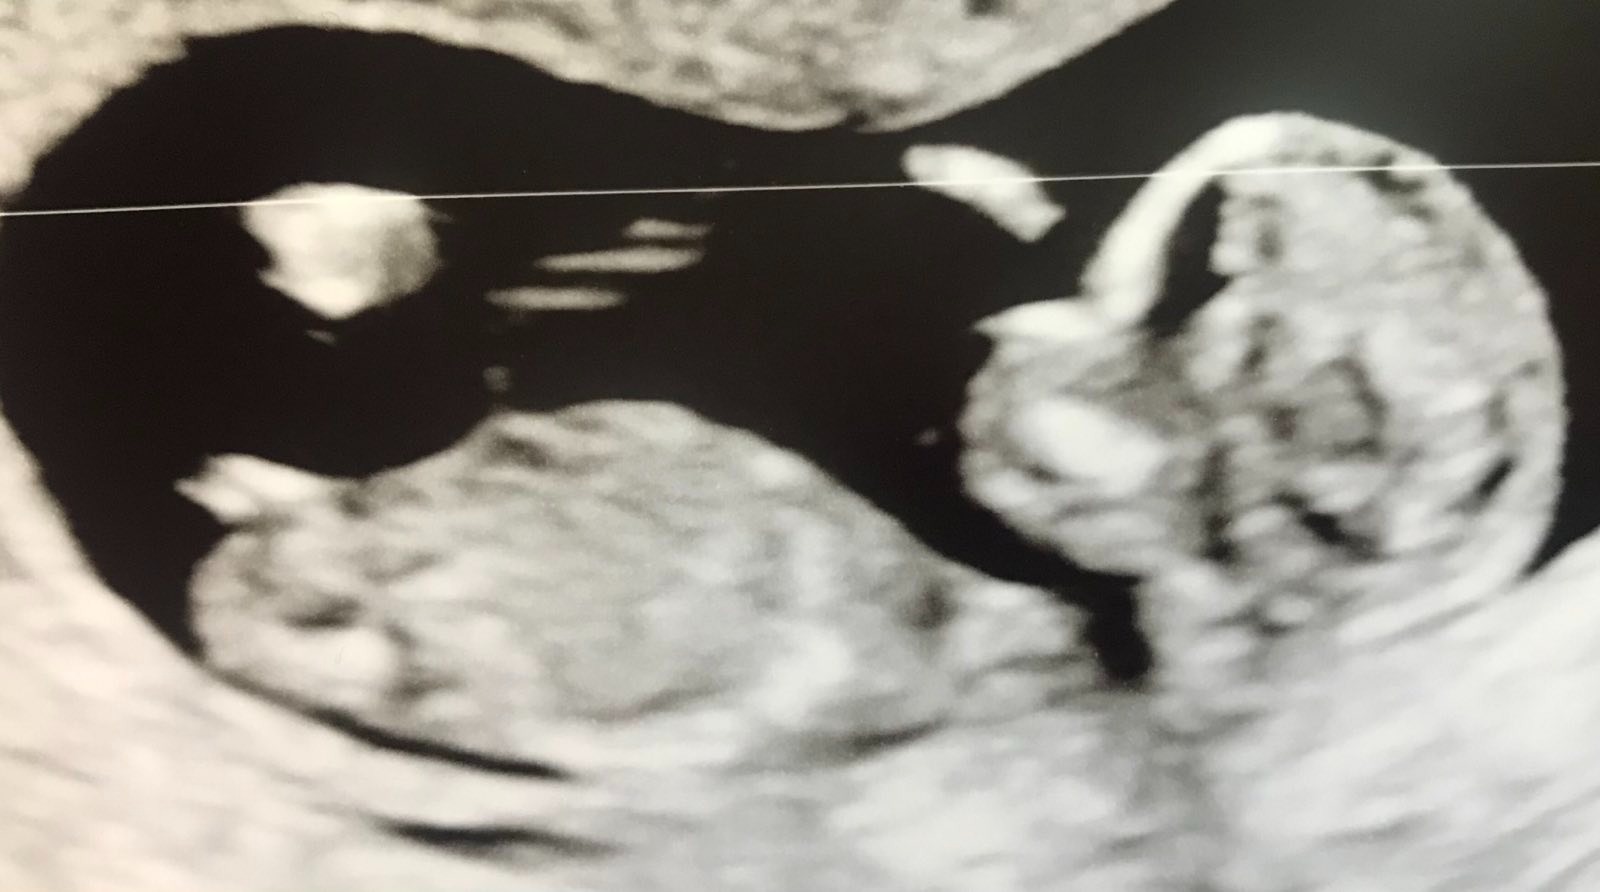

Osaako joku paremmin asiaan perehtynyt sanoa olisiko tuo jalkojen välissä oleva viiva nub?jos on niin tuon perusteella sanoisin tytöksi? Itsellä ollut koko alkuraskauden erittäin vahva poikafiilis, joten saa nähdä mitä käy

Nub saattaa vielä nousta, jos ollaan vasta 12 viikolla.

Ennuste muuttuu paljon varmemmaksi, jos päästään vähän pidemmille viikoille.

Mutta siis, vaikka jalat on vähän tiellä olen näkevinäni tyttö Nubin.

Lähetettiin ultrakuvat myös muutamalle sivustolle jossa asiantuntijoita ja sieltäkin saatiin aika varmat poikaveikkaukset!